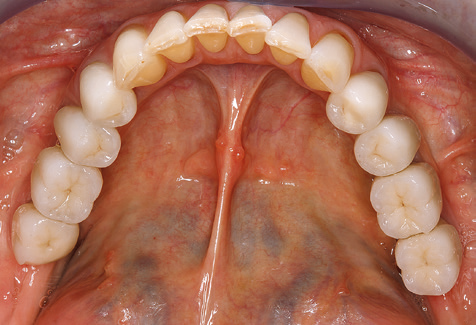

Eine 52­-jährige Patientin stellte sich nach Zahnverlust im 3. Quadranten erstmals 2004 vor. Sie hatte den Wunsch nach einer prothetischen Neuversorgung. Im Rahmen der parodontologischen und radiologischen Diagnostik zeigte sich ein ausgeprägter parodontologischer Behandlungsbedarf. Die Zähne 48, 28, 27 zeigten zudem eine infauste Prognose und wurden entfernt (Abb. 1). Nach der erfolgreich abgeschlossenen systematischen PAR­Therapie wurde eine festsitzende implantatprothetische Versorgung mit Insertion von fünf Implantaten in Regio 35, 36, 37 und 46, 47 durchgeführt. Die prothetische Versorgung der natürlichen Zähne erfolgte mit verblendeten Zirkonoxidkeramikkronen, die Implantate wurden mit zweiteiligen individuellen Zirkonoxidabutments und ebenfalls verblendeten Kronen aus einer Zirkonoxidkeramik versorgt (Cercon base colored, Dentsply Sirona Lab). Die definitive Insertion der prothetischen Versorgung erfolgte im Jahr 2005.

Aufgrund der bestehenden parodontalen Vorerkrankung erfolgte die unterstützende Parodontaltherapie (UPT) in den ersten Jahren in einem Drei­Monats­Intervall. Dabei zeigte die Patientin eine hohe Motivation und gute Compliance. Bei den jährlich erhobenen Sondierungsbefunden zeigten sich stabile parodontale Verhältnisse mit einem BOP­Index unter fünf Prozent. Aufgrund der stabilen parodontalen Situation und der guten Mitarbeit der Patientin wurde ab dem sechsten Jahr der prothetischen Funktionsphase das Recallintervall auf halbjährlich um­gestellt. Auch mit diesem veränderten Recallintervall zeigten sich bei der jeweils jährlichen Aufnahme des Parodontalstatus stabile parodontale Verhältnisse, ohne Zunahme der Sondierungstiefen und einem BOP­Index unter fünf Prozent (Abb. 2a und b).

Im Rahmen der Zehn­Jahres­Kontrolle zeigten sich keine Hinweise auf einen fortschreitenden parodontalen Attachmentverlust oder einen periimplantären Knochenverlust (Abb. 3).

Die Patientin befindet sich weiterhin in einem halbjährlichen Intervall für die UIT. Nachfolgend werden am Beispiel dieser Patientin die einzelnen Arbeitsschritte einer strukturierten UPT­Sitzung aufgezeigt, so wie sie nahezu unverändert über den gesamten Funktionszeitraum von immerhin zwölf Jahren durchgeführt wurden. Natürlich wurden über diesen Zeitraum einige neue Materialien und Geräte in das Konzept integriert. In diesem klinischen Fallbericht wird das aktuelle Material­ und Gerätekonzept präsentiert.

Abb. 9: Die Politur der zugänglichen Implantat­ und Zahnoberflächen erfolgt mit Polierkelchen und geeigneten Polierpasten. – Abb. 10: Die Reinstruktion zur Anwendung geeigneter Hilfsmittel bei der häuslichen Mundhygiene sollte ebenfalls Bestandteil der UPT sein. – Abb. 11a und b: Klinische Situation zwölf Jahre nach Insertion der prothetischen Versorgung. In diesem Zeitraum kam es lediglich zu einer Verblendkeramikfraktur am Zahn 47 und der Notwendigkeit einer endodontischen Behandlung am Zahn 12. Sämtliche Restaurationen sind noch in Funktion.

Für den klinischen Langzeiterfolg des parodontal kompromittierten Patienten ist die standardisierte und regelmäßige risikoadaptierte Betreuung im Rahmen der UPT der zentrale Baustein des Behandlungserfolgs. Dies gilt in besonderer Weise für Patienten, die nach erfolgreich abgeschlossener parodontaler Sanierung mit Implantaten versorgt wurden (Abb. 11a und b).